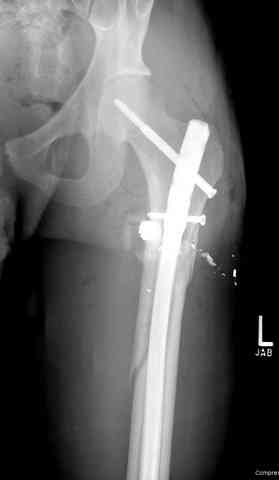

Здесь представлены несколько случаев лечения огнестрельного перелома

1 Проксимальный перелом бедра, антеградный гвоздь